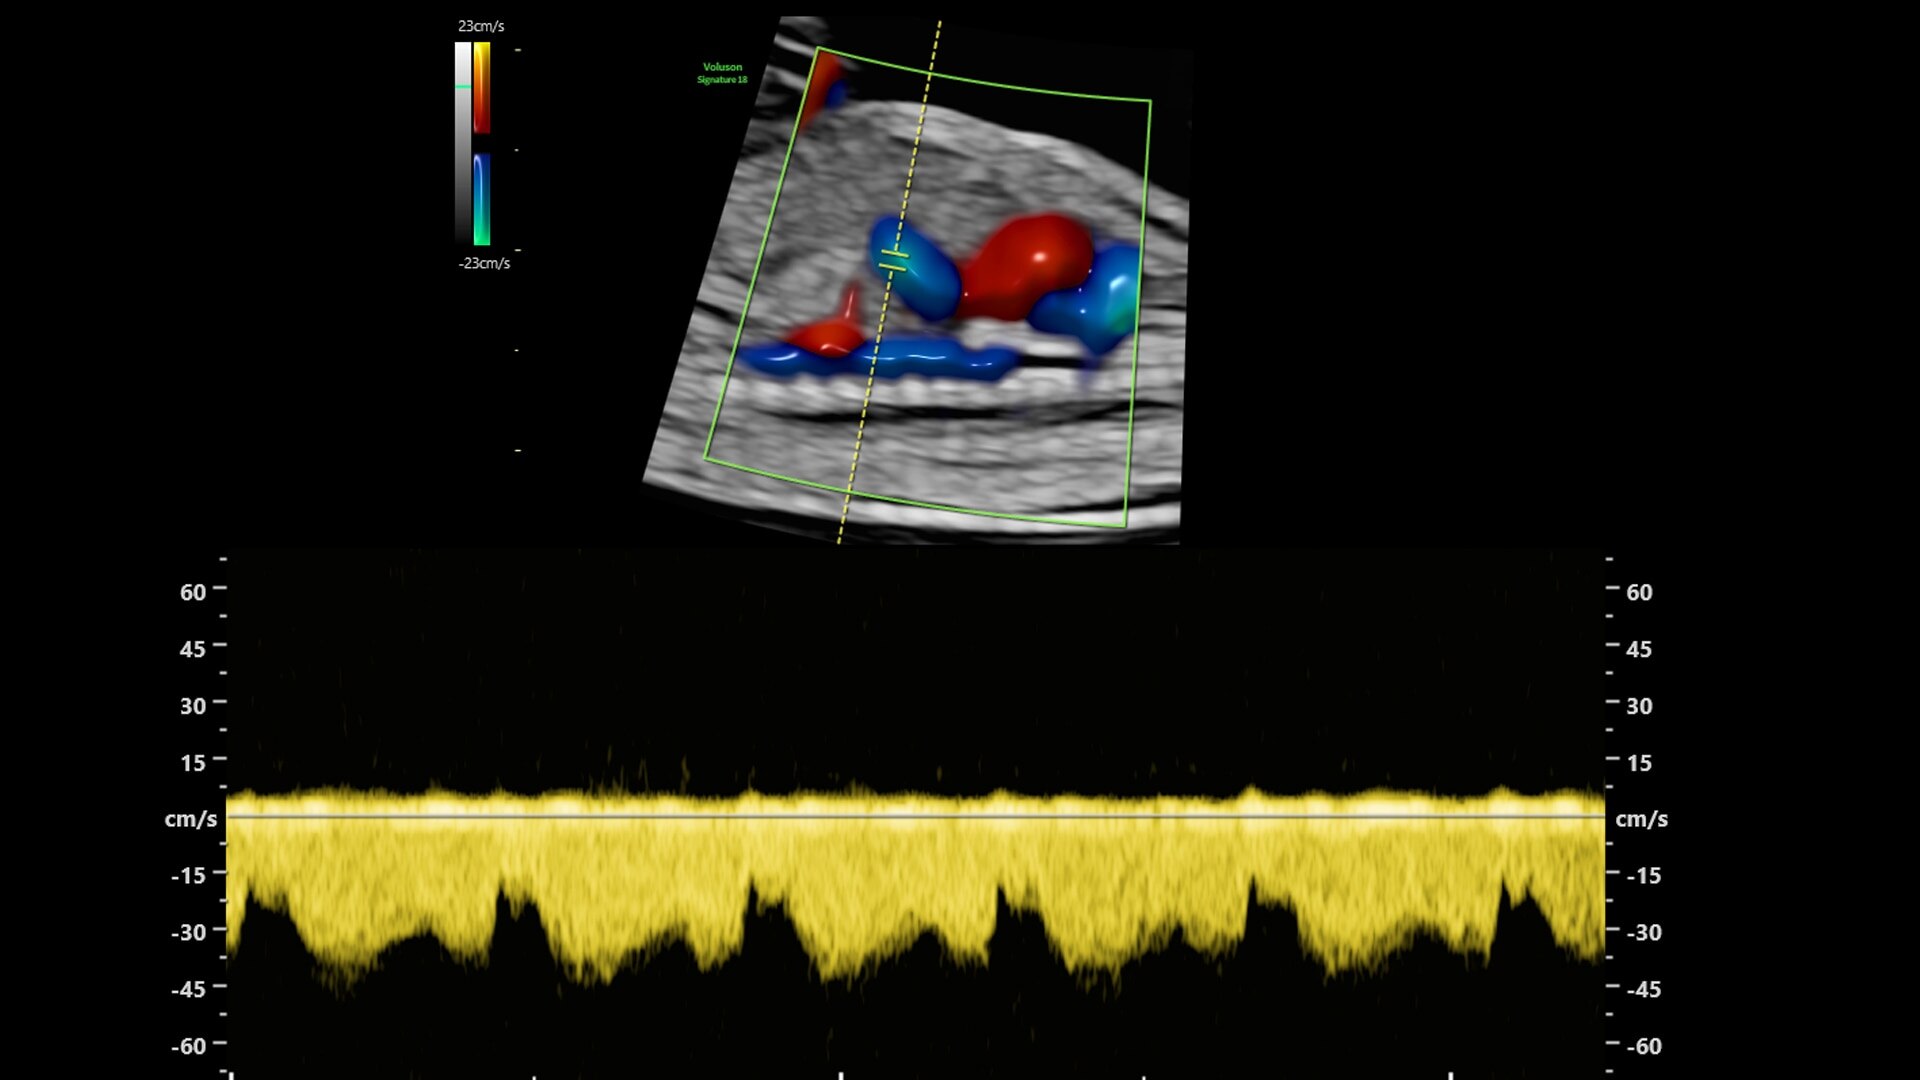

Reduce color and Doppler exam time by 56% with Flow Profiles

Fast, easy 3D-like blood flow visualization

Next level color Doppler delivers exceptional sensitivity for easy, fast visualization of blood flow, revealing even the tiniest vessels.

3-radiantflow-clinical-image-ci-en